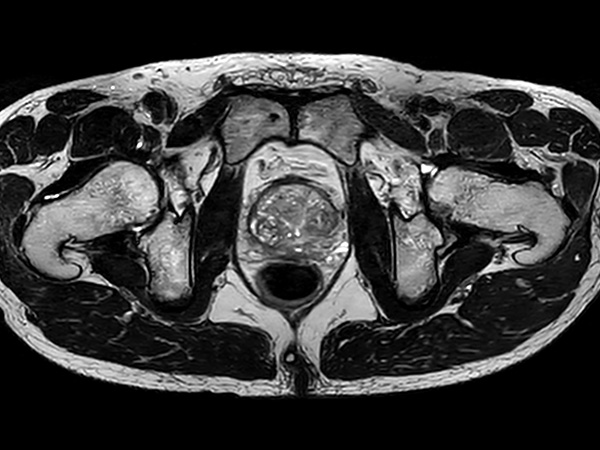

Fast Prostate imaging with SmartSpeed Precise

Kumamoto Chuo Hospital Japan